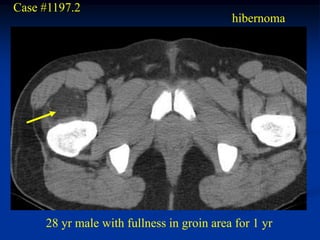

Case #1197.2

hibernoma

28 yr male with fullness in groin area for 1 yr

Case #1197.2 hibernoma 28 yr male with fullness in groin area for 1 yr

• 153.

T-1 Axial PD Gad

• 154.

Sag PD Sag Gad